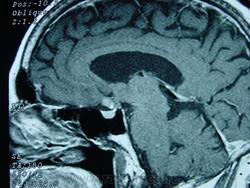

ГМ. Кавернома 2. Кавернома зрительного тракта. +

Кавернома зрительного тракта